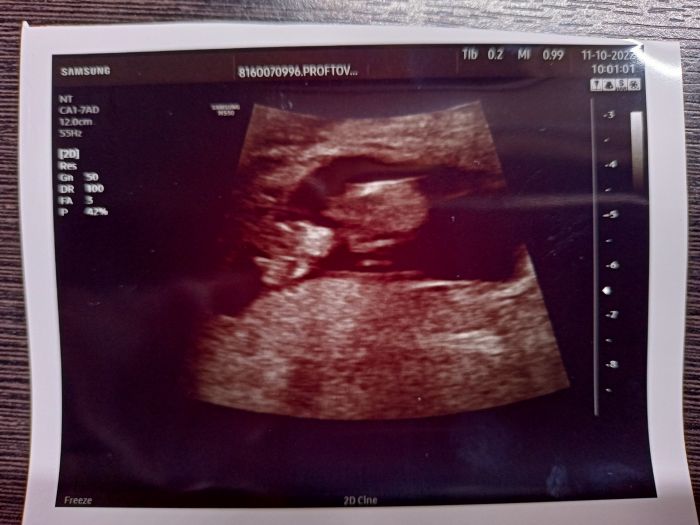

V utery jsem byla na dalsi kontrole, miminko je uplne v poradku - dnes jsem 11+0. Dostala jsem prukazku a 2.11. me ceka prvotrimestralni screening. Navic me doktorka dala kontakt na jinou diabetolozku, ktera by mi mohla pomoct vyhnout se komplikacim, ktere nastaly v minulem tehotenstvi z velke casti prave kvuli diabetolozce od Apolinare ( kde skoncim nyni znovu, nemam jinou moznost....)

...hmmm, jeste koukam, ze ta fotka je tedy dost k nicemu - ale pry na me Broucatko koukalo primo oblicejem